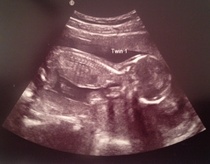

I feel like I'm bragging or something here but I just wanted to share that things went well at the hospital today and mum was able to make it after all. We even went to look for some big baggy trousers afterwards because all of a sudden I have nothing that fits my bottom half. I ended up buying 2XL pyjama bottoms with drawstrings. Beautiful soft cotton and very comfy - plain black so I am totally going to get away with dressing them up for going out!

Anyway, here are the twins at 16+1, today.

December 2014 Thread #4